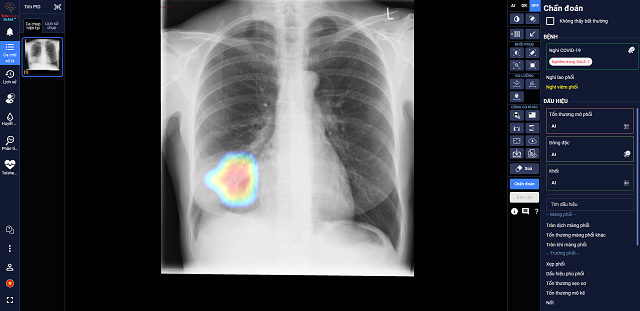

Sau hơn 1 năm nghiên cứu và phát triển, mới đây, VinBrain đã chính thức hoàn thiện sản phẩm DrAid cho COVID-19 với khả năng giải toàn diện bài toán COVID-19 từ hỗ trợ chẩn đoán tới tiên lượng điều trị dựa trên ảnh X-quang ngực thẳng.

Trong các bệnh viện thu dung điều trị COVID-19, DrAid cho COVID-19 giúp các bác sĩ đánh giá mức độ tổn thương phổi của bệnh nhân COVID-19 qua các ngày, từ đó đưa ra các chỉ định điều trị kịp thời và hiệu quả cho bệnh nhân.

Theo đánh giá của các bác sĩ tại Trung Tâm Y Tế Kỳ Anh – Hà Tĩnh, AI đã giúp đỡ các bác sĩ khá nhiều khi theo dõi tổn thương qua các ngày, nhận diện rõ ràng là tổn thương lan rộng như thế nào. Ngoài ra, AI cũng giúp bác sĩ nhận diện các tổn thương nhỏ dễ bỏ sót.